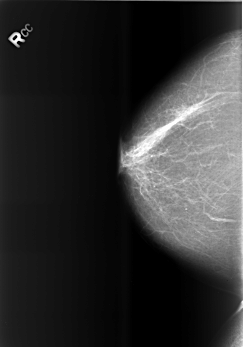

Digital Database for Screening Mammography

Volume: benign_13 Case: B-3466-1

B_3466_1.RIGHT_CC

RIGHT_CC LINES 5552 PIXELS_PER_LINE 3880 BITS_PER_PIXEL 12 RESOLUTION 50 NON_OVERLAY